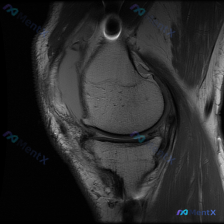

病例读片:主诉半月板异常,但这张MRI没看到明显问题? 整理了一份有意思的膝关节MRI读片病例,核心矛盾是临床提示半月板异常,但单张影像没找到对应病变,分享一下分析思路。 --- 病例基本影像信息 这是一张膝关节矢状位MRI单张切片,不是用户最初提到的肘部影像。 影像基础评估 - 定位:膝关节矢状位...

看到这个病例挺有代表性,整理了完整的分析思路分享给大家。 病例与影像基础信息 这是一份单张膝关节矢状位MRI影像,临床关注点是"半月板异常",需要基于现有影像做分析。 影像的核心征象整理如下: 1. 序列与定位:膝关节中部偏内侧矢状位,考虑为PDWI或T1加权像,适合显示半月板、韧带解剖结构 2....

看到一个有意思的影像讨论病例,整理一下资料和思路分享给大家。 病例背景 提问:单张膝关节冠状位MRI图像,问题是图像中可见的异常是什么,提示半月板异常。 影像初步分析 先确认这张影像的基本信息:这是膝关节冠状位MRI,对比良好,骨髓信号正常,可以看到股骨远端、胫骨近端、内外侧关节间隙、半月板和侧副韧...

看到一个很典型的临床-影像矛盾病例,整理出来和大家分享思路。 病例核心信息 这是一张膝关节矢状位MRI单张图像,临床关注点为「半月板异常」,我们先来看影像的全面评估结果: 1. 骨骼结构:股骨远端、胫骨近端、髌骨轮廓完整,无明显骨皮质中断或骨折 2. 关节软骨:股骨、胫骨关节面软骨信号均匀,无明显剥...